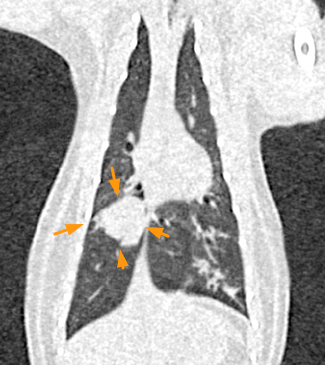

어린 고양이에게 폐에 결절이 발견될 경우 통상적으로는 저연령이기 때문에 종양성 질환을 후순위로 두는게 합리적인 판단이긴 하다.

하지만 어리다는 이유로 종양성 질환을 절대 배제해서는 안되는 이유로 제시할 논문이라 하겠다.

물론 이 논문의 증례는 4세령의 고양이라 과연 어리다고 이야기 할 수 있는가? 라는 부분에서 약간 갸우뚱 하다.